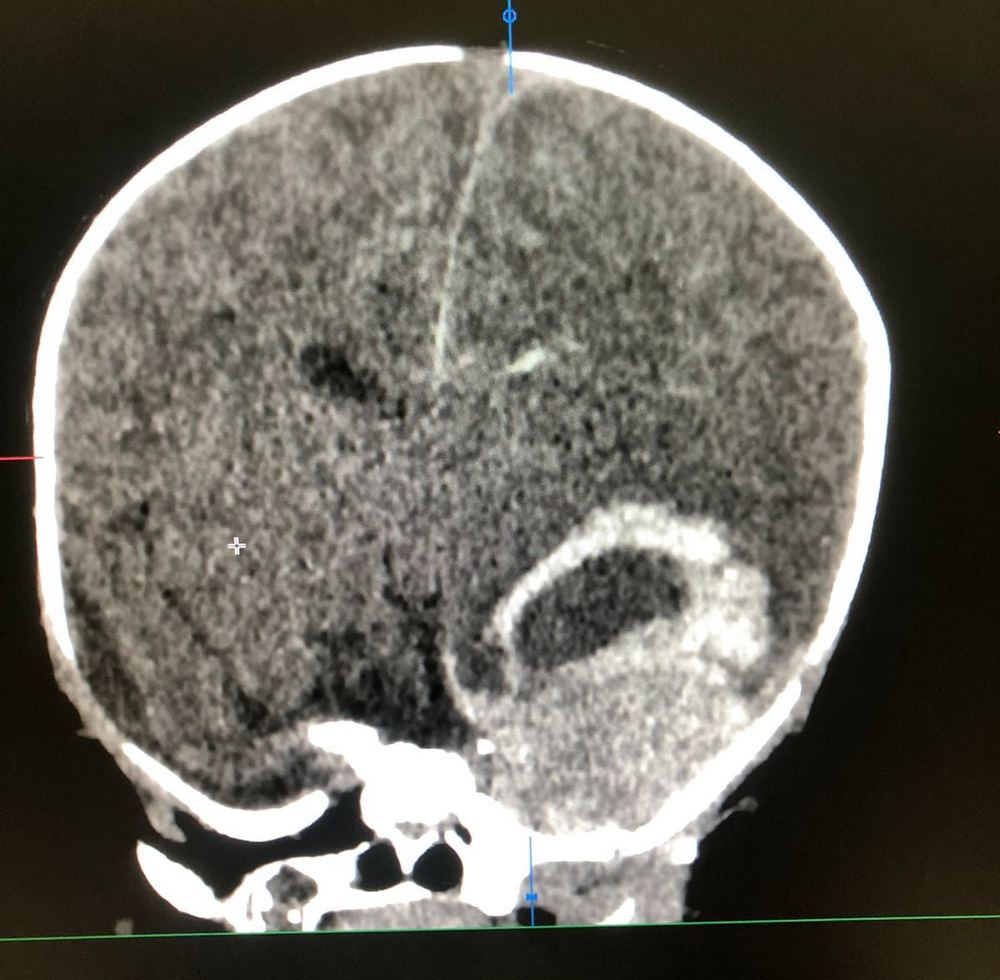

Фото предоставили в областной детской больнице

В приёмный покой областной детской больницы в экстренном порядке 21 октября поступил ребёнок в возрасте 38 дней. Его сразу же направили в отделение реанимации с диагнозом: острое нарушение мозгового кровообращения (ОНМК, инсульт), внутримозговая гематома, дислокационный синдром, постгеморрагическая анемия тяжелой степени, ДВС-синдром (синдром диссеминированного внутрисосудистого свёртывания) и кома I-степени.

Была проведена декомпрессионная трепанация черепа и удалены внутримозговые гематомы.